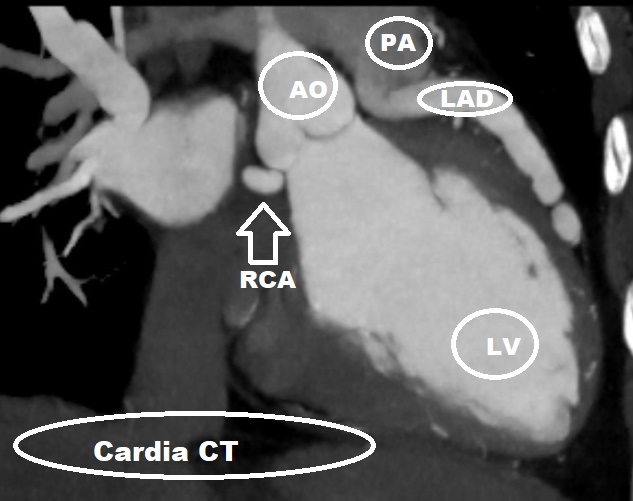

We report a case of a 52-year-old male who presented with progressive exertional dyspnea and clinical signs of heart failure. Electrocardiography showed no typical signs of ischemia. Laboratory findings showed significantly elevated N-terminal pro-B-type natriuretic peptide. Transthoracic echocardiography revealed severely impaired left ventricular ejection fraction. Coronary angiography was performed and showed a complex double coronary anomaly with an anomalous origin of the left coronary artery from the pulmonary artery with extensive collateralization from the right coronary artery supplying the left coronary system. Additionally, an anomalous origin of the circumflex artery from the right coronary artery with benign course, which is one of the most common coronary artery anomalies, was found. The diagnosis was subsequently confirmed by computed tomographic (CT) coronary angiogram with 3D reconstruction, which showed ectatic RCA arising from the right coronary sinus and the left descending artery arising from the pulmonary artery. Cardiac Magnetic Resonance (MR) demonstrated thinning of anterolateral wall of the left ventricle with sub endocardial delayed gadolinium enhancement.